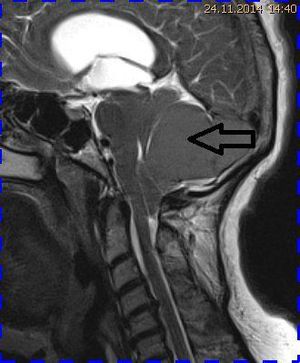

Abb. 1.2 Sagittales MRT (T2 TSE, 1 T): Streckfehlhaltung der HWS und oberen BWS, kein Frakturhinweis oder posttraumatische Myelopathie; die Kleinhirntonsillen reichen bis in das Foramen magnum

Das Fallbeispiel 1 zeigt im Verlauf eine Komplikation bei einer Arnold-Chiari-Malformation Typ 1 bei einem zum Zeitpunkt der Erstdiagnose 12-jährigen Jungen. Dieser hatte im Sportunterricht einen schweren Medizinball geköpft und ein Stauchungs-trauma der Halswirbelsäule erlitten. Nach anfänglich symptomatischer frustraner Therapie wurde er vom behandelnden Orthopäden zur MRT der HWS überwiesen. Es wurde eine Streckfehlhaltung und flachbogig rechtskonvexe Skoliose diagnostiziert, klinisch bestand ein Torticollis. Eine knöcherne oder ligamentäre Verletzung wie auch eine Schädigung des Rückenmarks bzw. eine intraspinale Bandscheibendislokation konnten bildmorphologisch ausgeschlossen werden.

Trotz weiterer Schmerz- und Physiotherapie konnte keine Beschwerdereduktion erreicht werden. 2 Monate später erfolgte eine MRT des Kopfes zum Ausschluss einer posttraumatischen Veränderung.

Bei dieser Untersuchung wurde übersehen, dass die Kleinhirntonsillen in das Foramen magnum disloziert waren und eine Arnold-Chiari-Malformation mit Erweiterung des 4. Ventrikels und des Aquäduktes inklusive Kleinhirntonsillentiefstand vorlag. Bei zwischenzeitlich auswärtig erfolgtem CT der HWS wurde eine Anlagestörung im kraniozervikalen Übergang beschrieben. Eine Kontrolluntersuchung des Kopfes weitere 4 Monate später dokumentierte neben einem medullären Ödem einen progredienten Tonsillentiefstand, der zur neurochirurgischen Behandlung mit operativer Erweiterung des Foramen magnum führte.